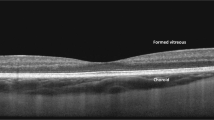

4D MIOCT imaging also helped guide the placement of the corneal graft in a partial thickness corneal transplantation. During the DSAEK procedure, only the posterior 10% cornea is replaced with a donor graft; therefore, the surgeon must insert, unfold and manipulate the graft beneath the remaining native cornea. Figure 8 and Supplementary Movie S5 show a 4D MIOCT recording of the graft unfolding after insertion with the corresponding surgical camera frames. While the folded graft (blue arrows) could be identified in the operating microscope, the axial proximity of the graft to native cornea was only visible with MIOCT. The surgeon then injected air to unfold the graft and compress the intervening space between the graft and cornea. MIOCT was used during the maneuver to monitor graft placement and confirm graft/host apposition. Failure to eliminate graft/host interface fluid would result in post-operative graft detachment and need for additional surgery to reattach the graft.

4D MIOCT-guided unfolding of graft below native cornea during human partial thickness corneal transplantation.

4D MIOCT imaging was necessary to determine the axial distance between the graft and native cornea, which was invisible through the operating microscope. (A) Frames from the surgical camera (top) and excerpts from a 4D MIOCT recording shown in B-scans (middle) and volumes (bottom) during graft insertion and unfolding (Movie S5). As the graft (GR) (blue) unfolded, the surgeon used 4D MIOCT data to monitor the graft/cornea interface (GCI) (orange) and to ensure graft/cornea apposition. The volumetric rate for was 0.5 volumes/second. An image artifact due to specular reflection (SR) (yellow) from the corneal apex is present in the middle of the volumes. Time stamps (black) are in seconds. The white rectangle in the volumes denotes the location of the B-scan. The green dashed box denotes the lateral MIOCT field of view. The volumetric MIOCT field of view was 6 × 10 × 10 mm.